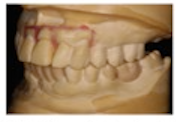

21歯とFH平面の角度118°

平均値より約3mm前方

セットアップモデル

下顎4前歯の矯正的坻出

前歯・側方歯の遠心移動

ブラケットは骨頂から

矯正による抜歯